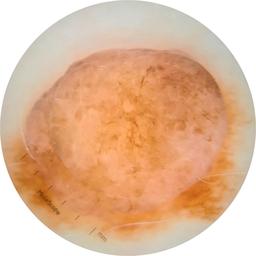

ISIC_9966288

811 x 811

Clinical

Field Value

acquisition_day 475

age_approx 50

anatom_site_1 Trunk

anatom_site_2 Posterior trunk

anatom_site_general posterior torso

concomitant_biopsy False

diagnosis_1 Benign

diagnosis_confirm_type single image expert consensus

family_hx_mm True

image_manipulation instrument only

image_type dermoscopic

lesion_id IL_7153617

patient_id IP_5835518

personal_hx_mm True

sex female